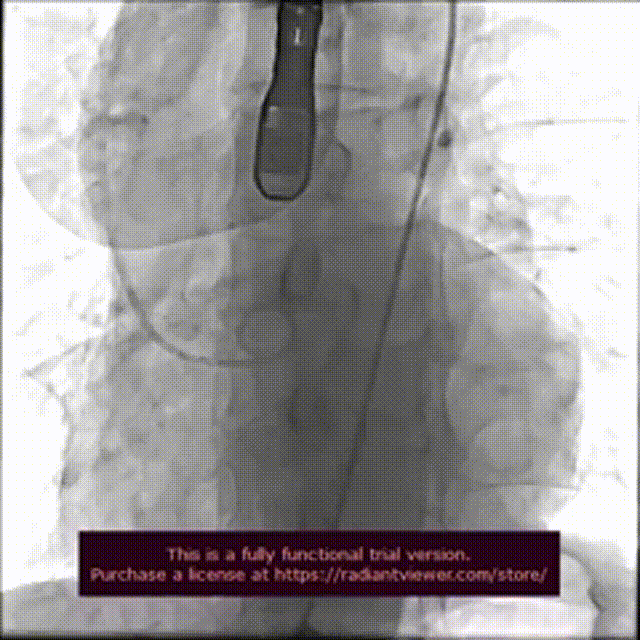

术前造影检查,主动脉瓣大量返流

圈套器辅助下,送入30mmVitaflow瓣膜

造影定位,可见无冠瓣叶较高

快速起搏条件下前期释放2/3瓣膜

造影显示瓣膜位置良好后完全释放

术后造影